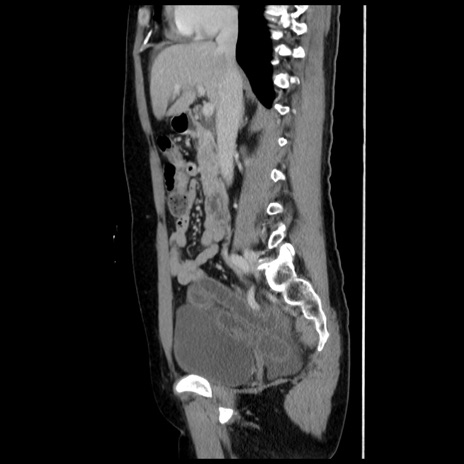

横断像